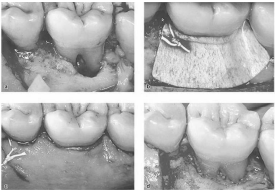

Analise as figuras abaixo.

Fonte: Lindhe et al., 2016.

A alternativa correta que descreve a cirurgia periodontal realizada e o grau de furca indicado é